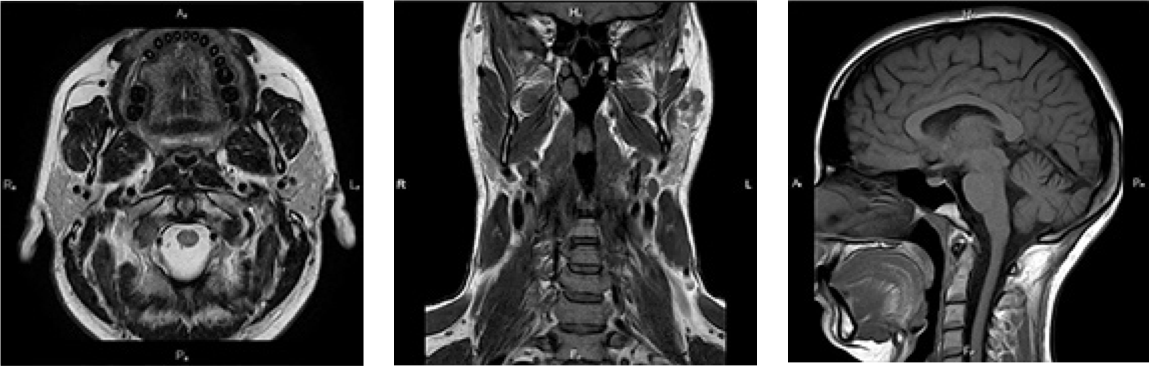

Neinvazivna dijagnostička metoda koja pruža detaljan uvid u strukture glave i vrata izvan mozga i kičmene moždine.

Pregled obuhvata pljuvačne žlezde, limfne čvorove, krvne sudove i mišiće regije glave i vrata. Pruža izuzetno detaljne slike sa visokom kontrastnom rezolucijom za preciznu dijagnostiku.

Naša 3T tehnologija omogućava vrhunski prikaz mekotkivnih struktura, što je od ključnog značaja za ranu detekciju patoloških procesa, procenu proširenosti tumora i stanja limfnih čvorova vrata.

Detaljan uvid u strukture glave i vrata izvan mozga i kičmene moždine uz vrhunski 3T prikaz i eliminaciju rentgenskog zračenja.